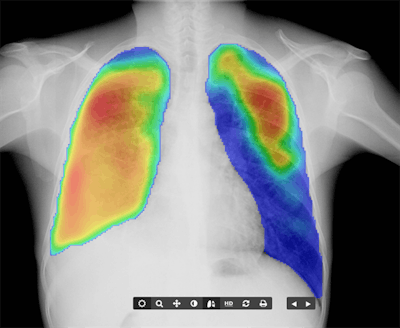

Canon Medical Systems is giving ECR 2020 attendees at look at digital radiography (DR) technology available through its subsidiary, Delft Imaging Systems, where a major focus is on developing software for tuberculosis (TB) screening, such as the CAD4TB computer-aided detection (CAD) application.

Although the World Health Organization has recommended systematic tuberculosis screening, many local regions lack the local expertise to read TB images, and thus incidence of the disease has not declined. CAD4TB can help by automatically detecting signs of TB for individuals who can then be sent on for additional definitive tests like the GeneXpert diagnostic assay.

CAD4TB is an algorithm that's been trained to detect pathology that's indicative of TB, such as diffuse textural patterns, focal patterns, and pleural-related abnormalities. The algorithm scans patient images and provides clinicians with a score that indicates the likelihood that a patient is infected with TB. Some 3 million people around the world have been scanned with CAD4TB, according to Canon.